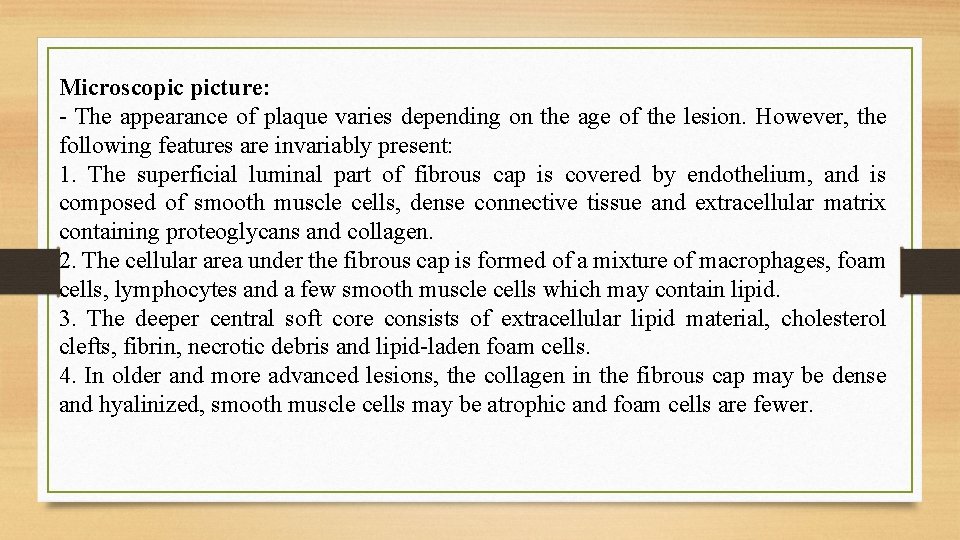

Microscopic picture: - The appearance of plaque varies depending on the age of the lesion. However, the following features are invariably present: 1. The superficial luminal part of fibrous cap is covered by endothelium, and is composed of smooth muscle cells, dense connective tissue and extracellular matrix containing proteoglycans and collagen. 2. The cellular area under the fibrous cap is formed of a mixture of macrophages, foam cells, lymphocytes and a few smooth muscle cells which may contain lipid. 3. The deeper central soft core consists of extracellular lipid material, cholesterol clefts, fibrin, necrotic debris and lipid-laden foam cells. 4. In older and more advanced lesions, the collagen in the fibrous cap may be dense and hyalinized, smooth muscle cells may be atrophic and foam cells are fewer.